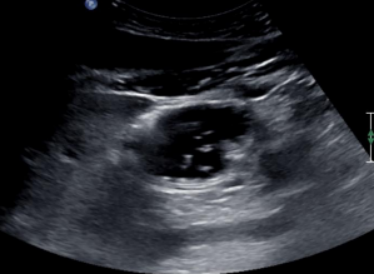

2. 胃窦内呈均匀一致的无回声或低回声4,或低回声中出现多个移动的点状高回声形似“繁星”5,宜评判为无渣清亮液体。当胃窦内回声呈均质增强时(6), 宜评判为浓稠液体

图片

4  无渣清亮液体低回声或无回声

5  无渣清亮液体,形似繁星